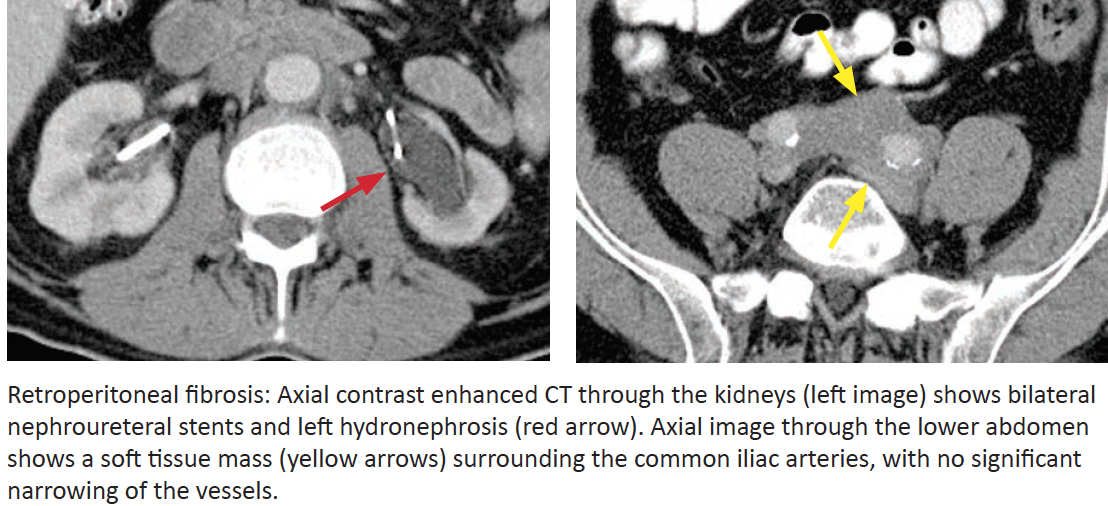

Retroperitoneal Fibrosis

What is it?

Compare to malignant retroperitoneal adenopathy.